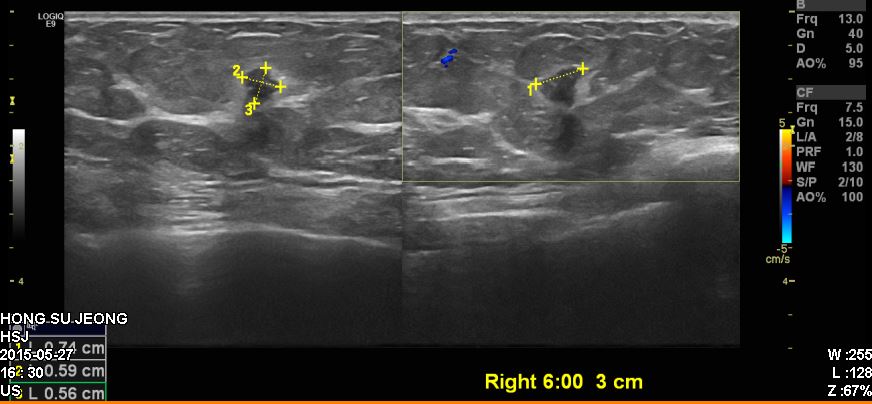

건진상 이상소견으로 내원하신 50대 환자분이십니다

본원에서 유방초음파 시행 후 우측유방에 혹 조직검사 시행하였고

침윤성유관암진단되었습니다.